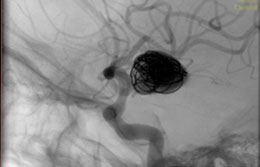

La paciente ingreso al Servicio de Hemodinamia el día martes 11 de febrero con un aneurisma cerebral gigante en la carótida izquierda y se le practicó una embolización; es decir una oclusión por dentro del mismo, donde se colocó un dispositivo denominado coils más un stent diversor de flujo. El procedimiento fue exitoso y contó con la colaboración de médicos neurointervencionistas del Instituto Oulton de la Ciudad de Córdoba.